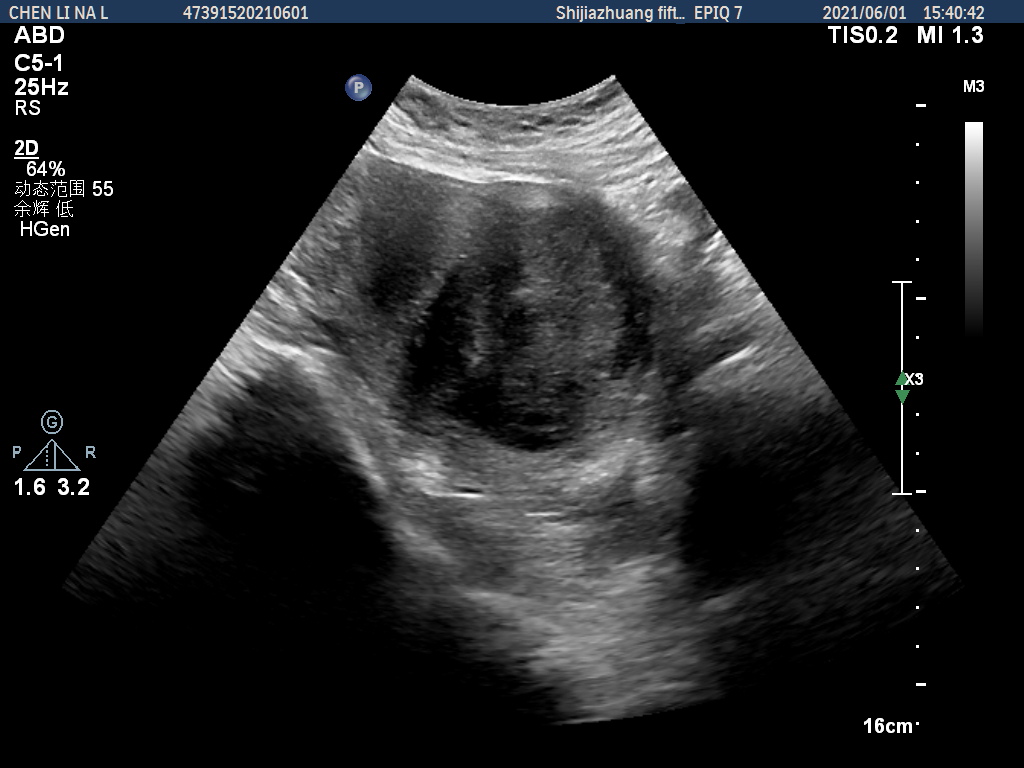

图1 子宫肌瘤治疗前,肿瘤大小。